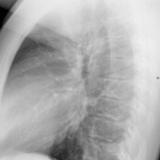

ASD 2 PA

Date: 03/17/2004

Views: 2413